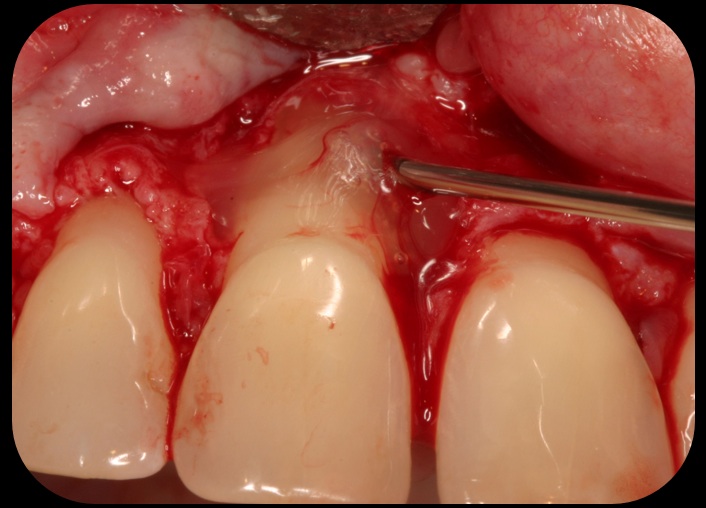

Then, too, are opportunities to prepare the site for regeneration by coupling therapies, applying an enamel matrix derivative, along with traditional bone grafts of demineralized freeze-dried bone allograft; potentially, gains in attachment with minimal probing depth and retained papilla may avoid the need for an implant (Figure 2 through Figure 7).

Application of enamel matrix derivative.

Fig. 4

Demineralized freeze-dried bone allograft.

Fig. 5

Evidence of clinical attachment gain.

Fig. 6